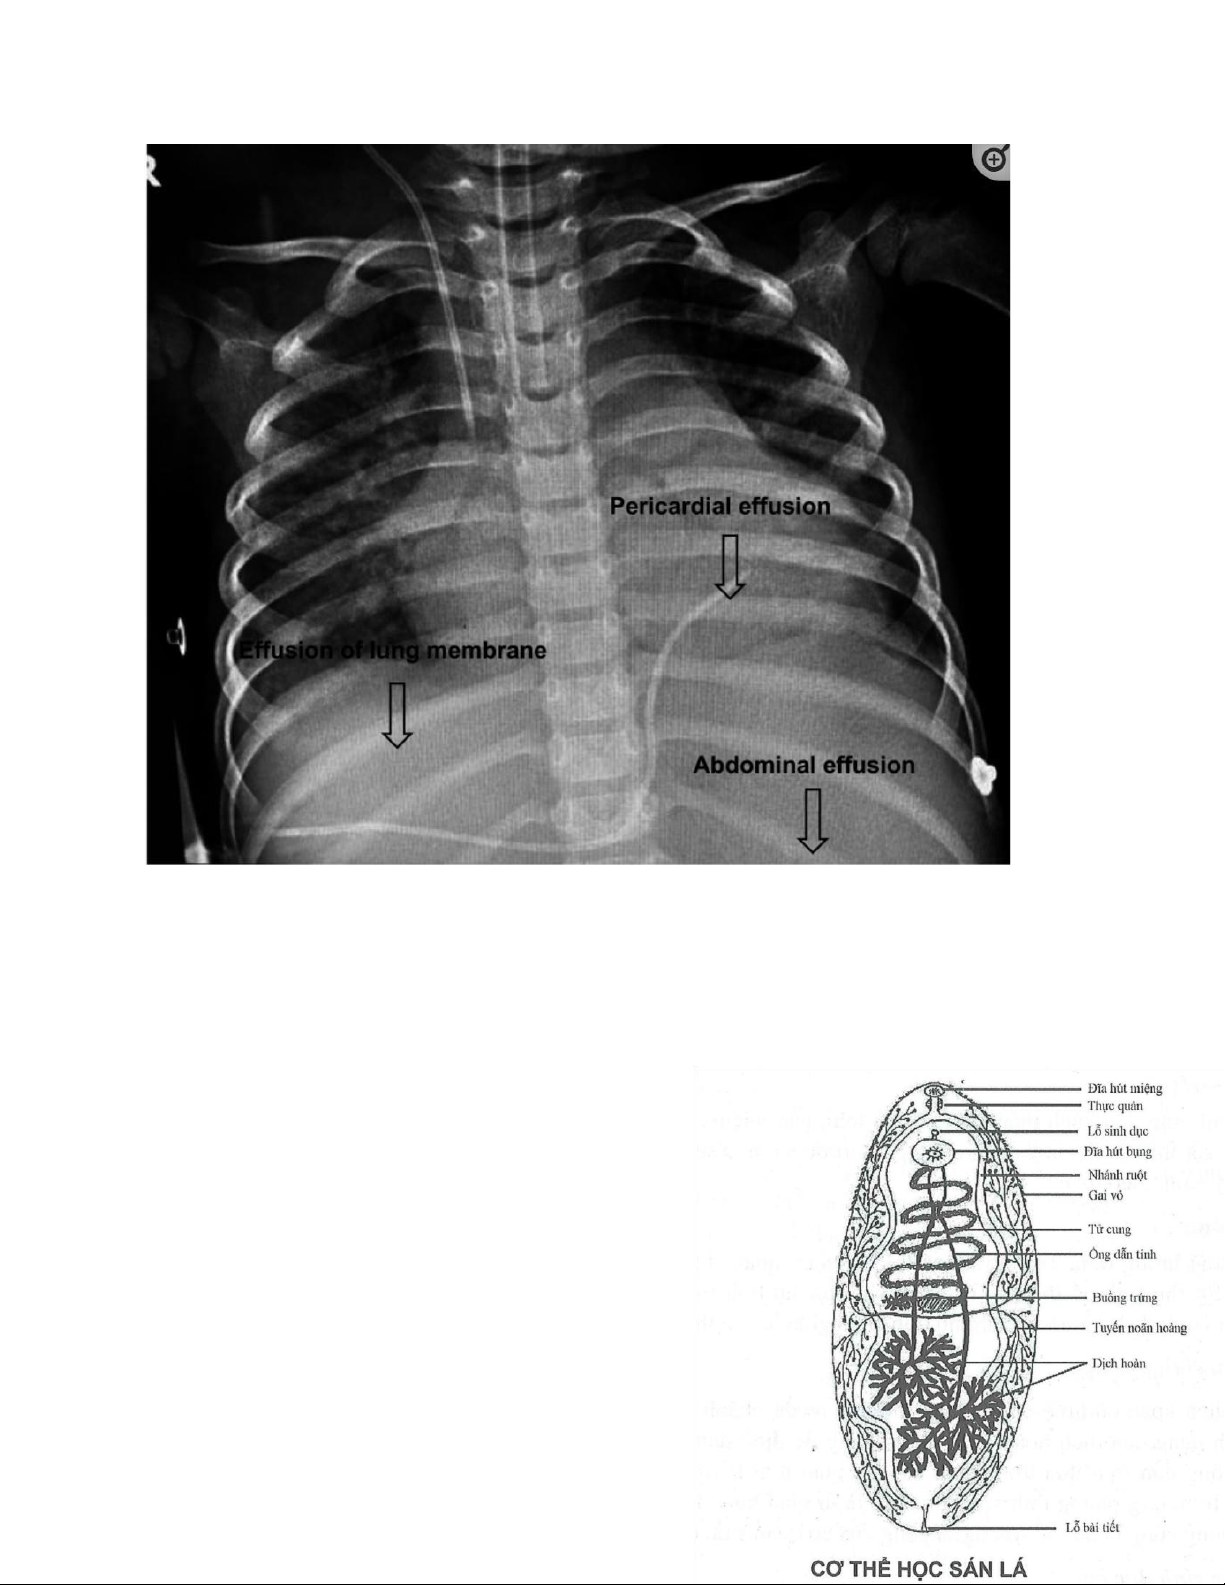

Một bé trai 3 tuổi, ở huyện Mường Khương, tỉnh Lào Cai, biểu hiện đầu tiên là đau bụng, ho, tức

ngực và sốt (39 độ). Ban đầu được chẩn đoán là viêm phế quản, việc điều trị bằng thuốc kháng

sinh tỏ ra vô ích. Hình ảnh khối u xuất hiện dưới lề phải 20 ngày sau. Tràn dịch màng phổi, màng

ngoài tim và ổ bụng được quan sát thấy ở US và X – quang. Tăng bạch cầu ái toan là 53.4 % trong

máu, 75% trong tràn dịch phổi và 80% trong tràng dịch ổ bụng. IgG là 25,38 (bình thường là 3,3 -

6,2) và IgE là 3000 (bình thường là 0 – 230). Tính dương tính của huyết thanh học cho thấy hiệu

giá là 1/3200 (OD=1,6). Không tìm thấy trứng trong phân, gợi ý nhiễm trùng trong giai đoạn cấp

tính. Trẻ hồi phục hoàn toàn sau khi điều trị triclabendazole 20 mg/kg (1 viên cho 15 kg). Không

có thành viên nào khác trong gia đình bị nhiễm bệnh. Bé đã từng ăn rau thủy sinh. lOMoAR cPSD| 39651089

Hình ảnh: Tràn dịch màng phổi, màng ngoài tim và ổ bụng khi chụp X – quang do Fasciola spp

nhiễm ở một bé trai 3 tuổi.

Nguồn: Early Postnatal and Preschool-Age Infection by Fasciola spp.: Report of Five Cases from

Vietnam and Worldwide Review (2020), Nguyen Thanh De.